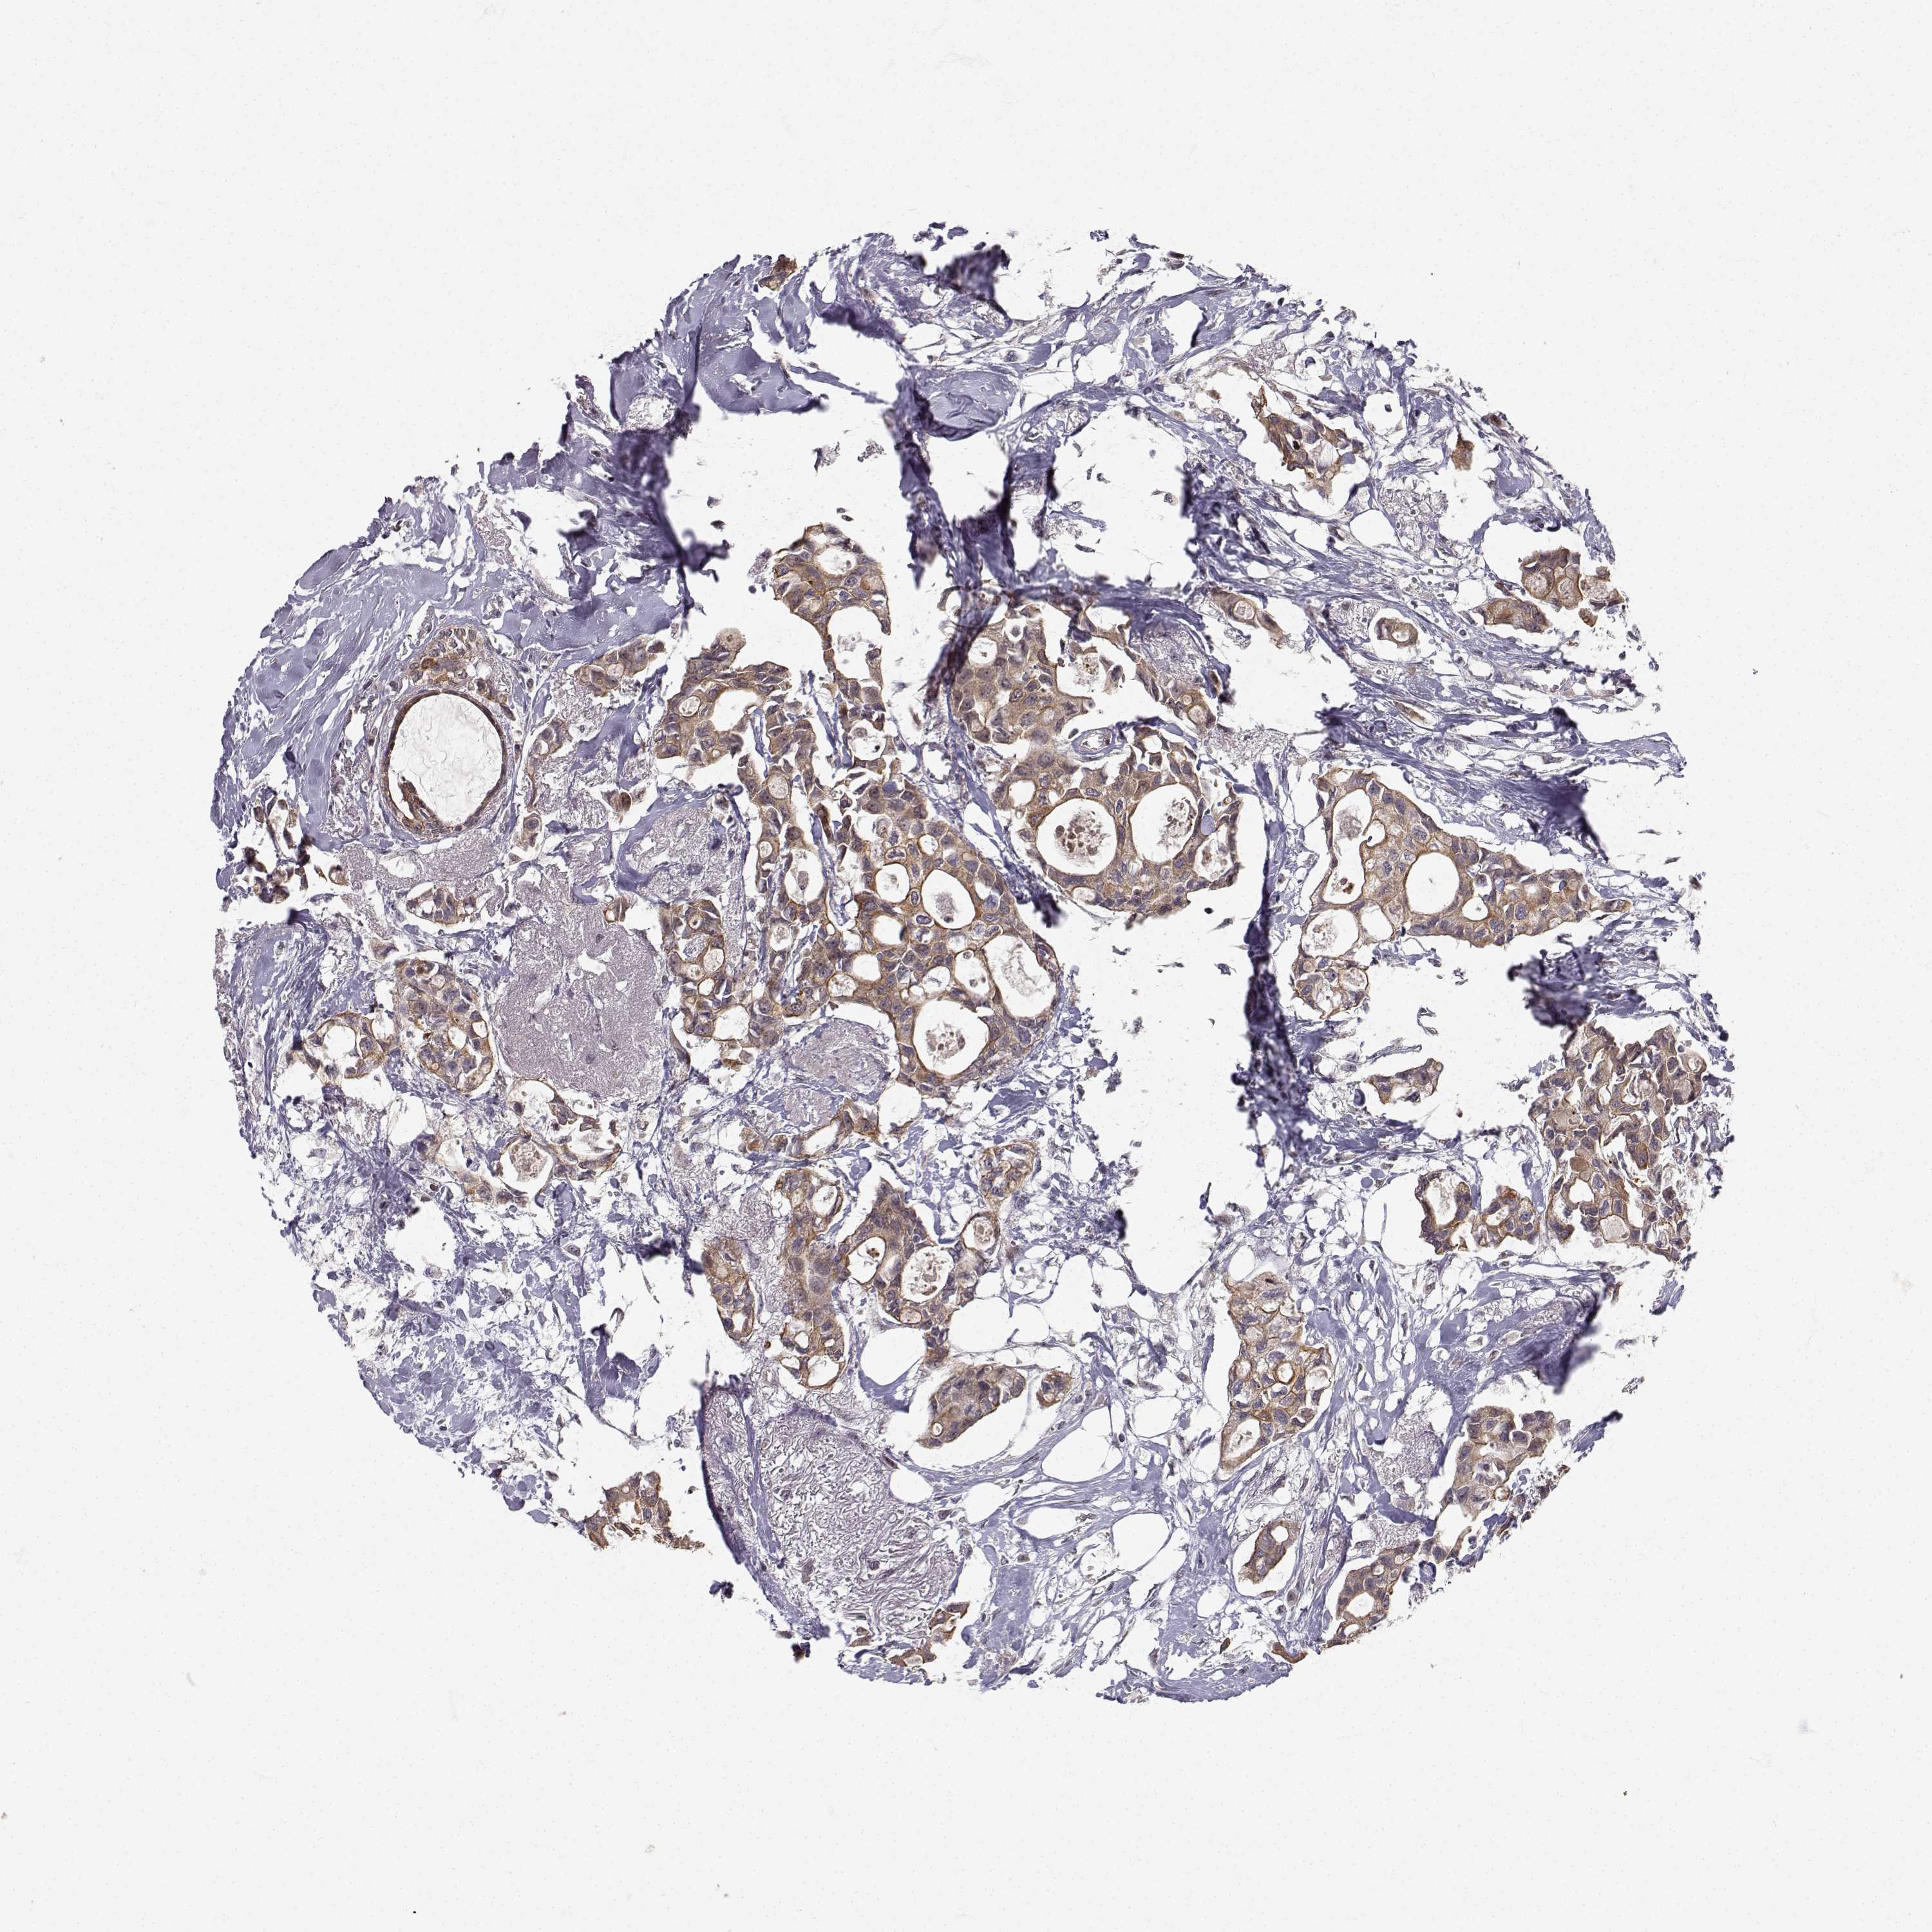

CANCER BREAST CANCER Show tissue menu

BRCA TCGA BRCA VALIDATION PROTEIN EXPRESSION

Breast cancer

Human cancer